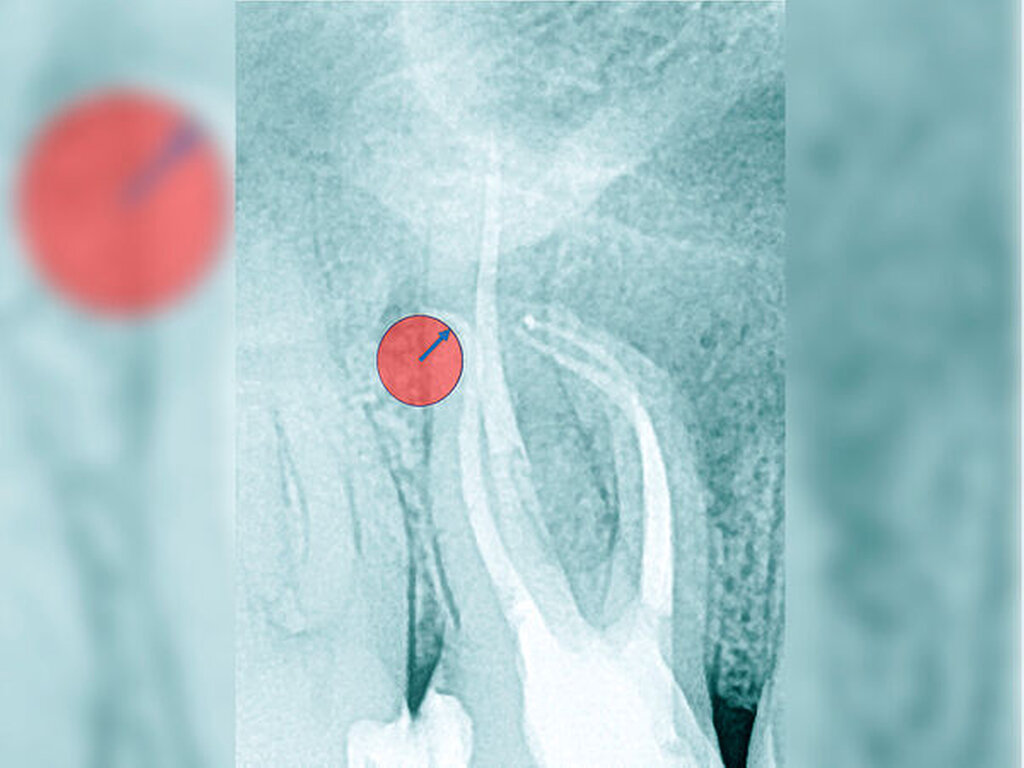

Die Schwierigkeit in der Therapie nimmt zu, wenn die Wurzelkanalkrümmung mehr als 30 Grad beträgt, der Krümmungsradius abnimmt (enge Krümmung) oder Mehrfachkrümmungen vorliegen [Duke et al., 2015; Pedulla et al., 2020]. Typisch für Mehrfachkrümmungen sind vor allem mesiale Wurzelkanäle unterer Molaren (Abbildung 4).

Sollte eine Konfluenz beider mesialer Wurzelkanäle am unteren Molaren vorliegen, kommt es zu einem abrupten Richtungswechsel und Instrumente können leichter frakturieren oder Stufen präparieren, so dass die Arbeitslänge nicht mehr erreicht werden kann.